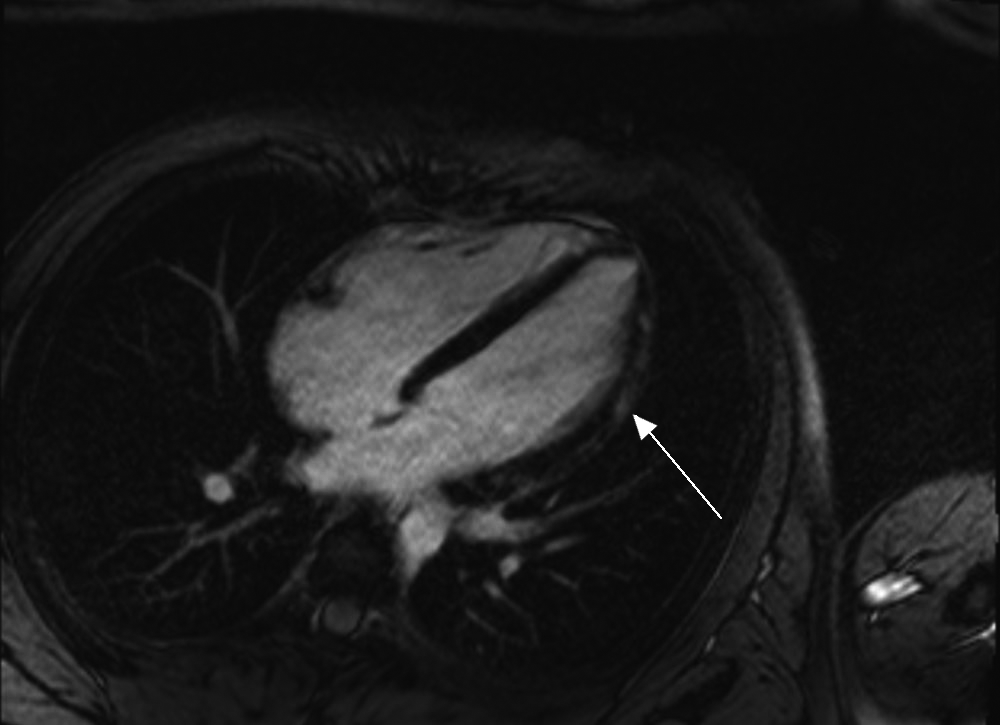

Transthoracic echocardiography showed normal biventricular function with no pericardial effusion. Cardiac magnetic resonance imaging showed normal left ventricular size and mildly impaired systolic function with hypokinesis of the mid and apical lateral segments associated with epicardial late gadolinium enhancement (Box 2), consistent with myocarditis.